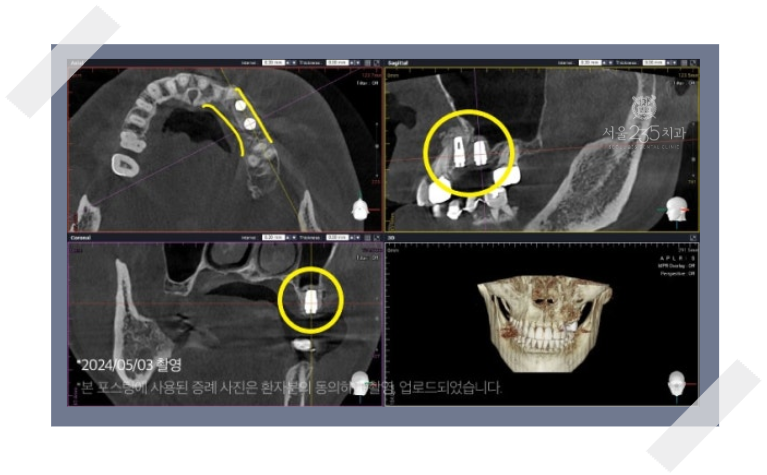

이러한 케이스는 아래와 같은 단계적 접근이 필요합니다.

(1) 문제 치아 발치 및 염증을 완벽하게 제거

(2) 잇몸과 뼈가 건강하게 아물 수 있도록 수개월의 회복기간 갖기

(3) 회복 후 부족한 뼈를 재건하는 뼈이식을 시행하고 계획된 위치에 임플란트 식립.

(때로는 뼈이식 후 다시 수개월을 기다려 뼈가 단단해진 것을 확인한 후 임플란트를 심기도 함)